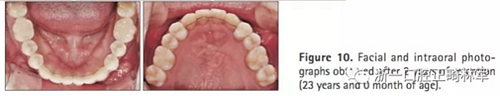

2年后隨訪提示治療結果得到保持(圖10,11,表1-3),不同階段的頭側重疊結果見圖12。